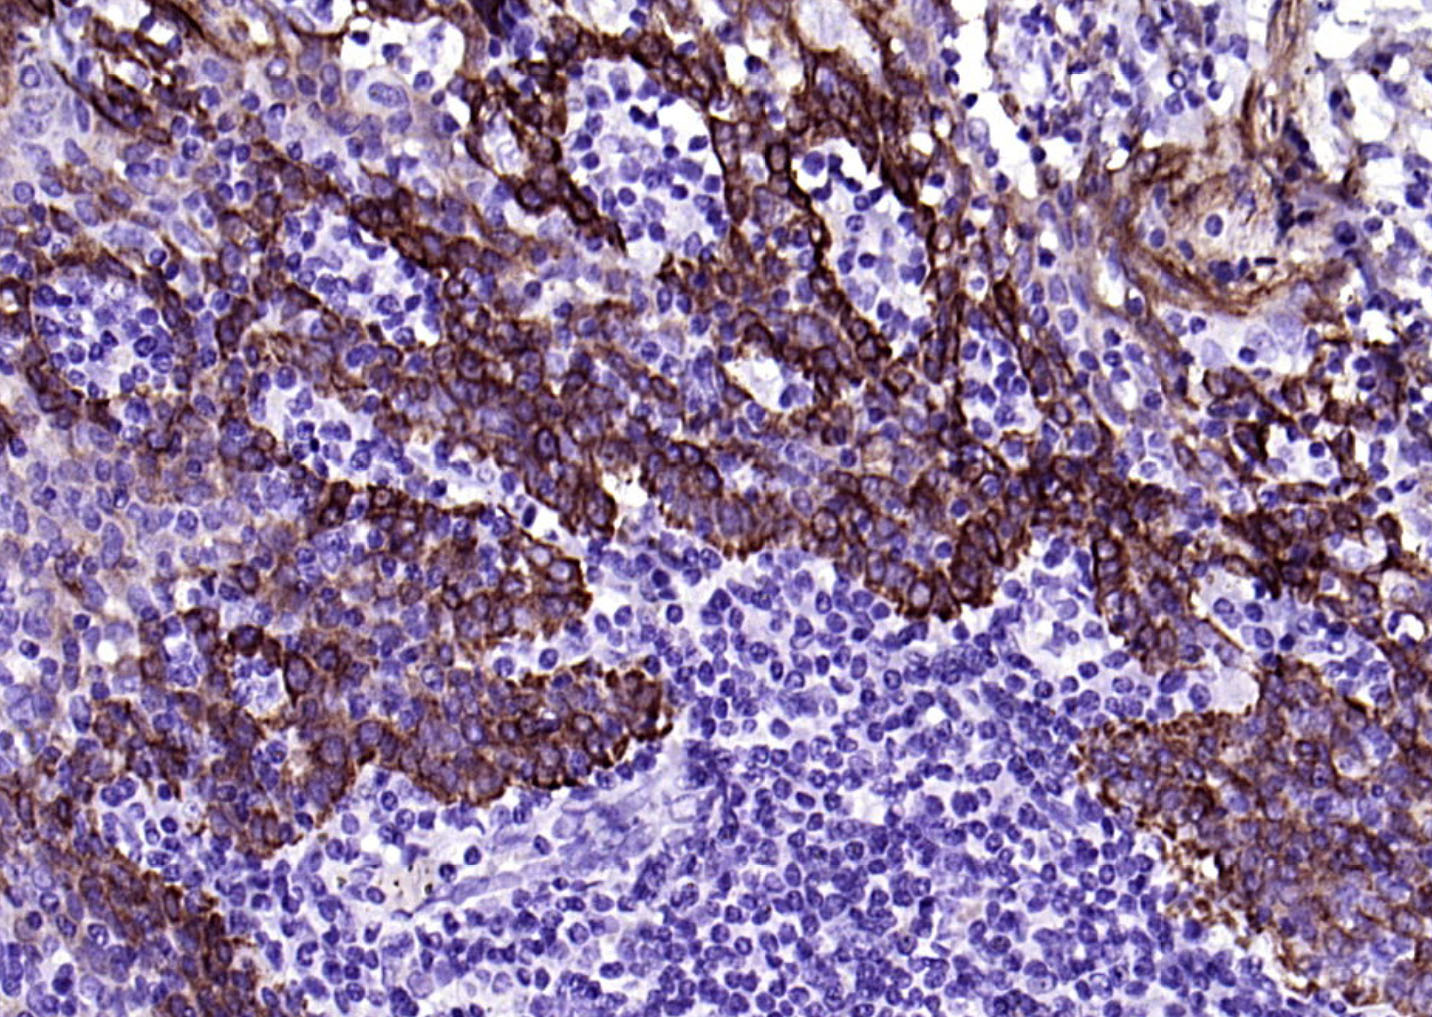

IHC-PHuman1:100-500

细胞角蛋白17单克隆抗体-bsm-33087M细胞角蛋白17单克隆抗体-bsm-33087M细胞角蛋白17单克隆抗体-bsm-33087M细胞角蛋白17单克隆抗体-bsm-33087M细胞角蛋白17单克隆抗体-bsm-33087M细胞角蛋白17单克隆抗体-bsm-33087M细胞角蛋白17单克隆抗体-bsm-33087M细胞角蛋白17单克隆抗体-bsm-33087M细胞角蛋白17单克隆抗体-bsm-33087M细胞角蛋白17单克隆抗体-bsm-33087M细胞角蛋白17单克隆抗体-bsm-33087M细胞角蛋白17单克隆抗体-bsm-33087M